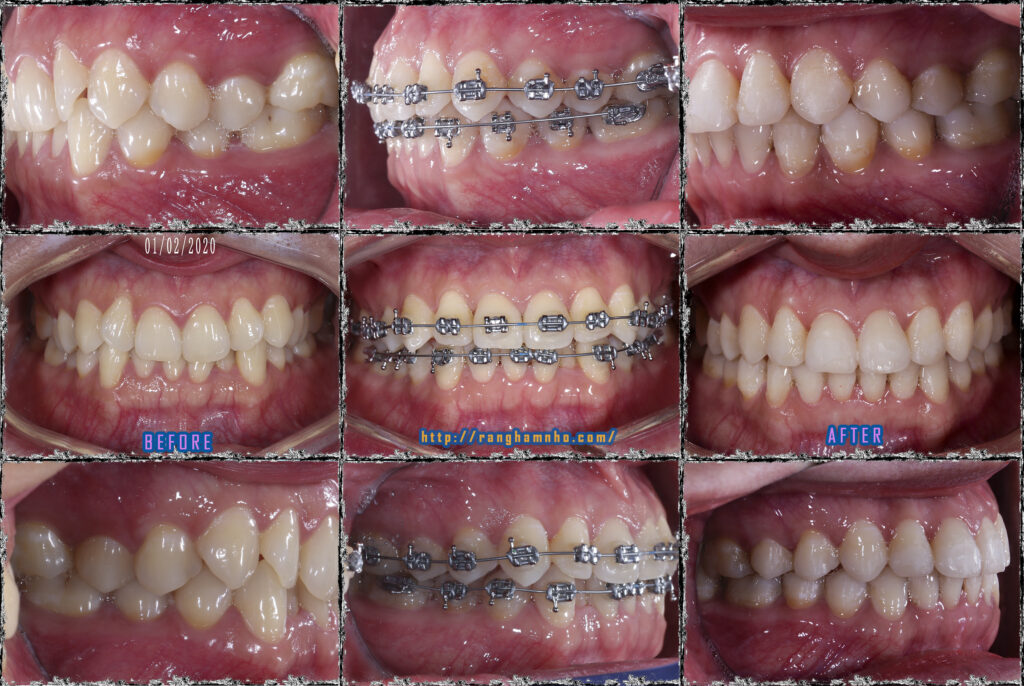

Bệnh nhân có cung hàm vuông, răng chen chúc cả hai hàm, khuôn miệng cười không đẹp. Gắn mắc cài kim loại truyển thống, sử dụng dây cung nong Damon qua các giai đoạn theo trình tự: San bằng, sắp đều, xử lí thiếu khoảng, đóng khớp cắn & tinh chỉnh, tháo niềng.